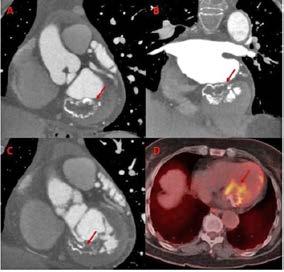

Se realizó una tomografía computarizada (TC) con contraste de forma emergente, que mostró una disección aórtica iatrogénica tipo A focal de origen en la zona 0 del cayado con extensión al tronco braquiocefálico derecho (1) sin afectar al resto de troncos supra-aórticos, cayado o aorta descendente (Figuras 1 y 2); además del hematoma

Figuras 1 y 2: Prótesis aórtica migrada y disección aórtica focal tipo A, de origen en la curvatura menor del arco aórtico (zona 0) hasta la bifurcación de la arteria braquiocefálica derecha; sin afectación de del resto de troncos supra-aórticos, del resto del cayado aórtico o de la aorta descendente.

Dia 1: Implante de TAVI

Dia 3: Cese de sangrado. Reinicio de anticoagulación

Dia 2: Anemización. Transfusión de hematíes

Dias 8 y 9: Pseudoaneurisma radial derecho: Diagnóstico e intervención

Dias 16: Disección distal de arteria radial derecha: Diagnóstico e intervención Ingreso

Dia 2: Disección aórtica tipo A

Dia 2: Hematoma cervical derecho

Alta +22

Dia 7: Angio-TC de control

• Estabilidad de disección aórtica

• Reducción del hematoma cervical

Dia 2: Agudización de trombopenia

Administración de bolus de corticoides

Figuras 3: Timeline de eventos y complicaciones que tuvieron lugar desde el ingreso hasta el alta, en orden cronológico.